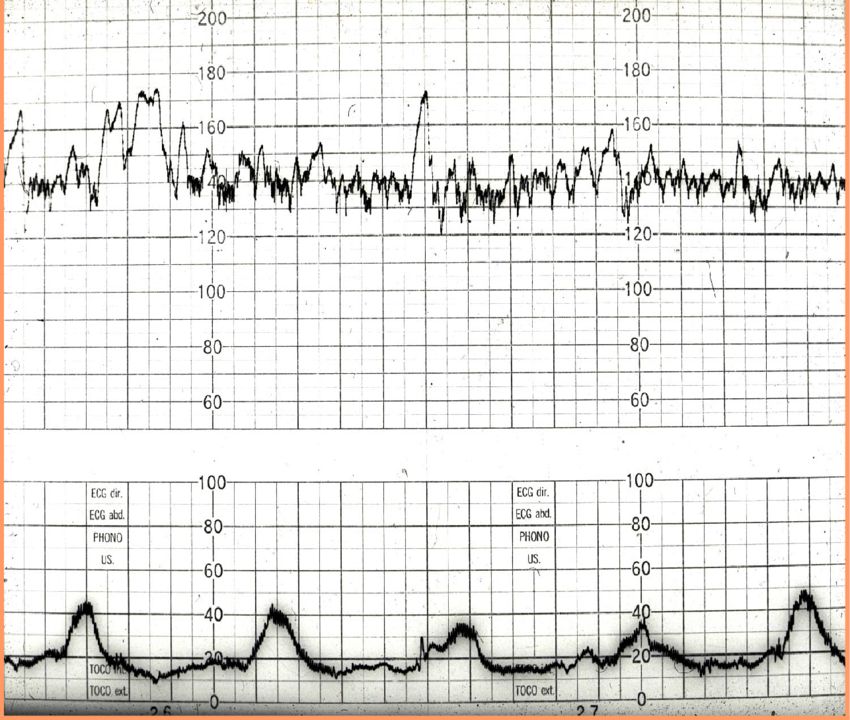

(Total Questions - 17)Q.1. Read the CTG report

Correct Answer : B

Q.2. Read the CTG report

Correct Answer : D

Q.3. What's the CTG report?

Q.4. What's the CTG report?

Correct Answer : C

Q.5. What's the CTG report?

Q.6. Whats the CTG report?

Correct Answer : A

Q.7. Whats the CTG report?

Q.8. Read the CTG

Q.9. What's the CTG report?